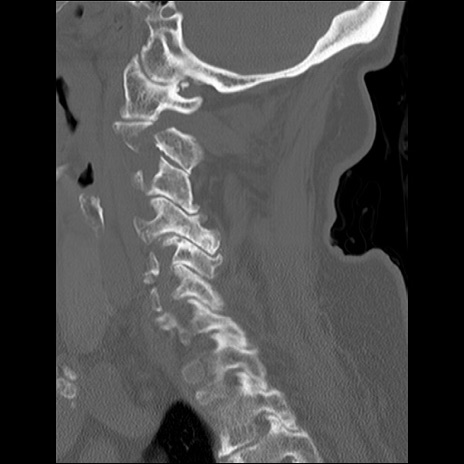

症例48 頚椎CT(矢状断像)

頚椎CT